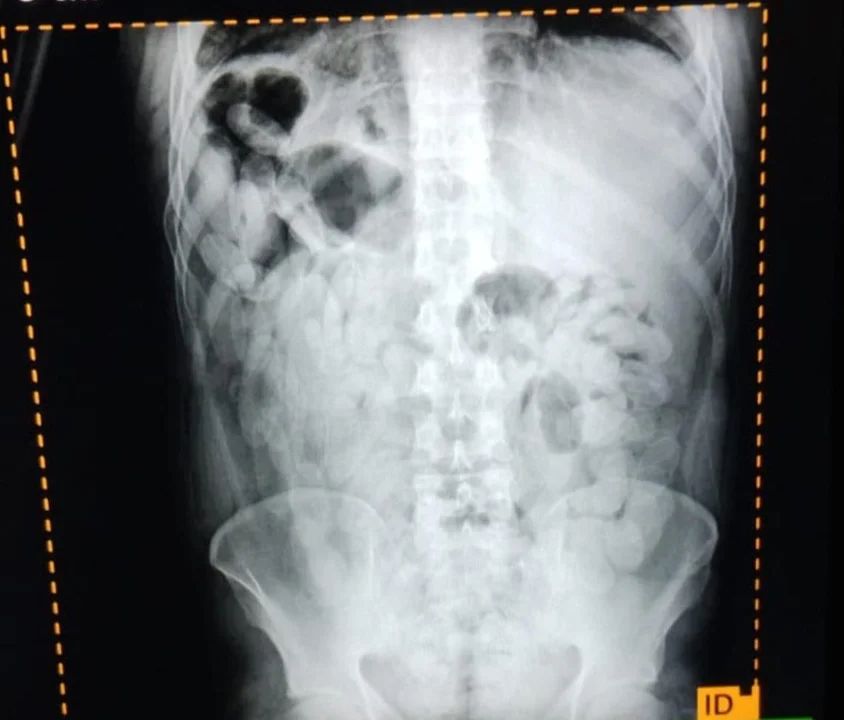

Ante la sospecha de la modalidad de traslado de estupefacientes conocida como “capsulero” y con el objetivo de preservar la integridad física de las personas, se solicitó la intervención de una ambulancia y se dispuso el traslado de los pasajeros al nosocomio local. A través de placas radiográficas se constató la presencia de cuerpos extraños compatibles con cápsulas ingeridas.

Posteriormente, los involucrados evacuaron un total de 180 cápsulas que, sometidas a la prueba de campo narcotest, arrojaron resultado positivo para cocaína, con un peso total de 2,102 gramos.